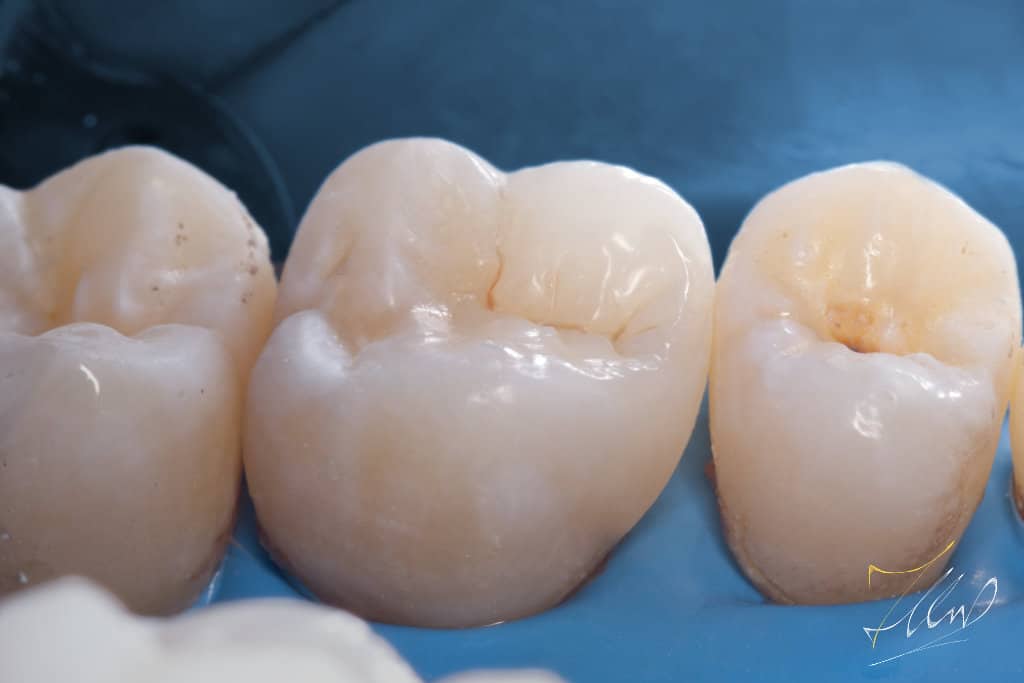

Final situation (pre polishing).

Final gloss for long lasting stain free restoration.

Buccal view shows the final contour and shape of buccal cusp.

The final palatal view demonstrates precise and secure contact placement, ensuring minimal stagnation and facilitating easy cleaning